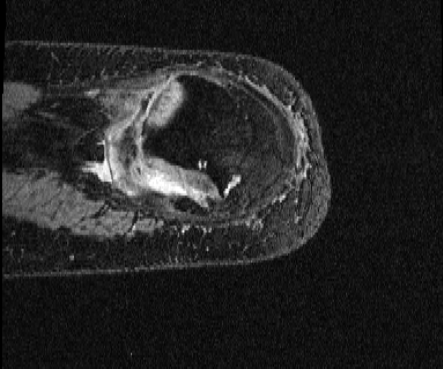

OAI Knee MRI We train and test on the split published with [22], with 2532 training examples and 301 test pairs from the Osteoarthritis Initiative (OAI) [16]444https://nda.nih.gov/oai. We evaluate using the mean Dice score of tibial and fibial cartilage. To compare directly to [22, 7, 23] we train and evaluate at [80x192x192].

| Moving Image | Warped Image | Fixed Image | Moving Image | Warped Image | Fixed Image |